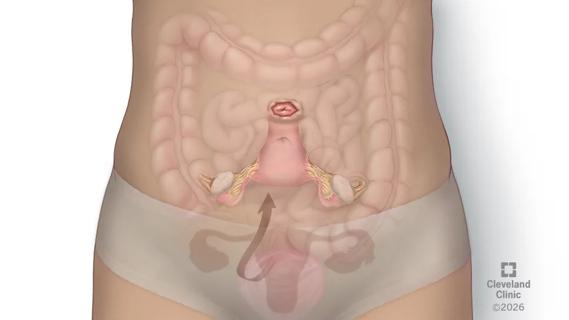

December 10, 2025/Neurosciences/Case Study

Nerve Transfer Surgery Restores Arm Function to 14-Year-Old With Ewing Sarcoma

Case study of radial-to-axillary nerve transfer for tumor-related deltoid nerve injury